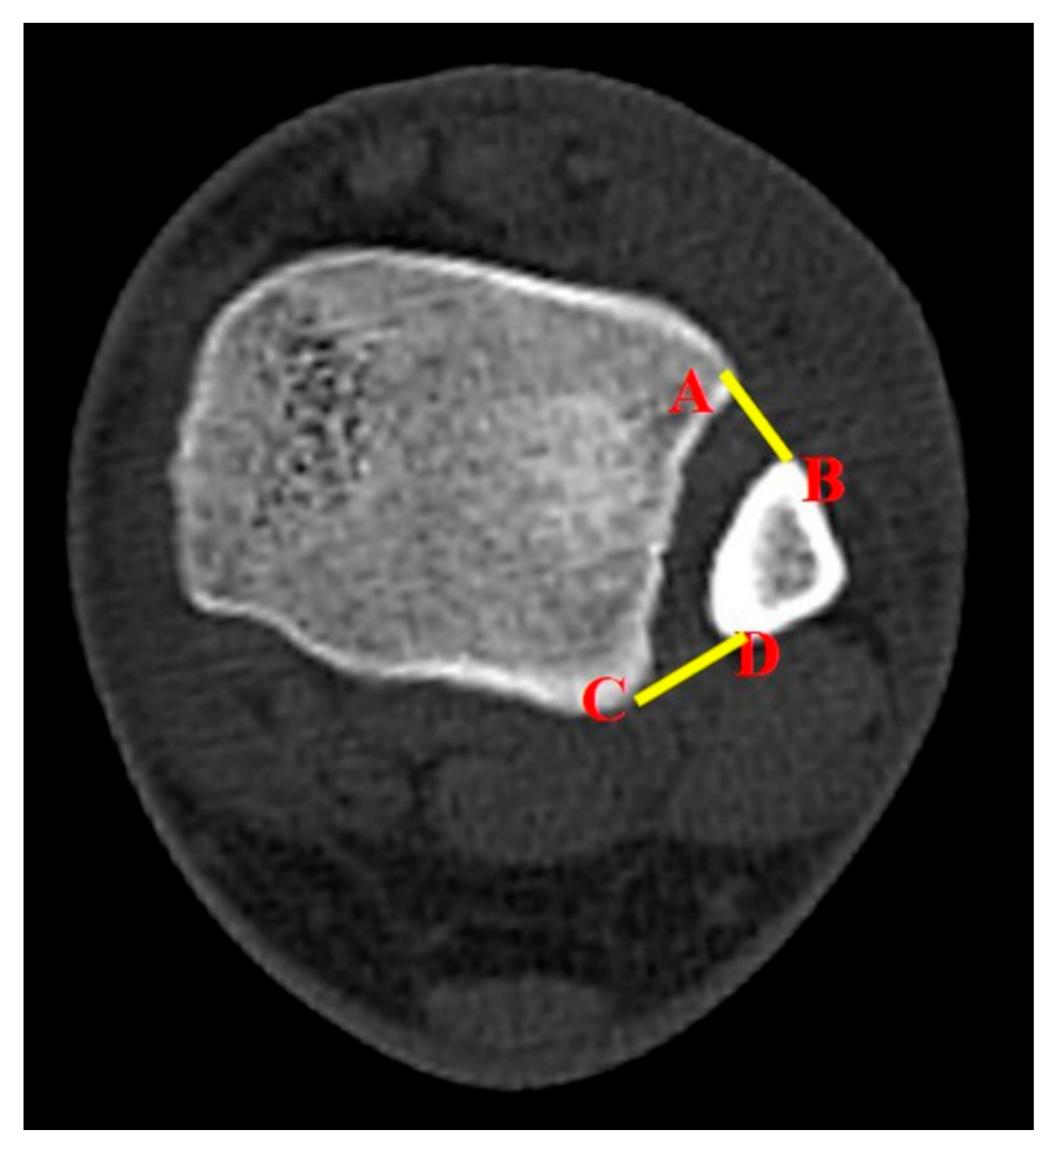

The study also utilized a new parameter to evaluate syndesmotic injuries. The surface area of syndesmosis (SAS) was measured 1.0 cm and 1.5 cm above the tibial plafond. From here, the researchers named them SAS 1.0 and SAS 1.5, respectively. The method for measurements of SAS 1.0 and SAS 1.5 was established by a consultative meeting made up of specialist in ankle joint trauma (SWL, CHP, BSK). The inferior border of the tibial plafond was first identified on the axial section and cross-referenced with the coronal section with scout imaging using CT scan. Each parameter (SAS 1.0 and SAS 1.5) was measured in the axial section of CT scan, which corresponds with the coronal section 1.0 cm and 1.5 cm above the tibial plafond (Figure 2). If there is a fracture line in the area to be measured at fibular site, that area was included as fracture diastasis.

Figure 2.

The surface area of syndesmosis, which was measured as a new parameter between four anatomic landmark points on the axial CT image; the points that link the anterior colliculus of the tibia (A), the most anterior aspect of the fibular (B), the posterior colliculus of the tibia (C), and the most posterior aspect of the fibular (D).